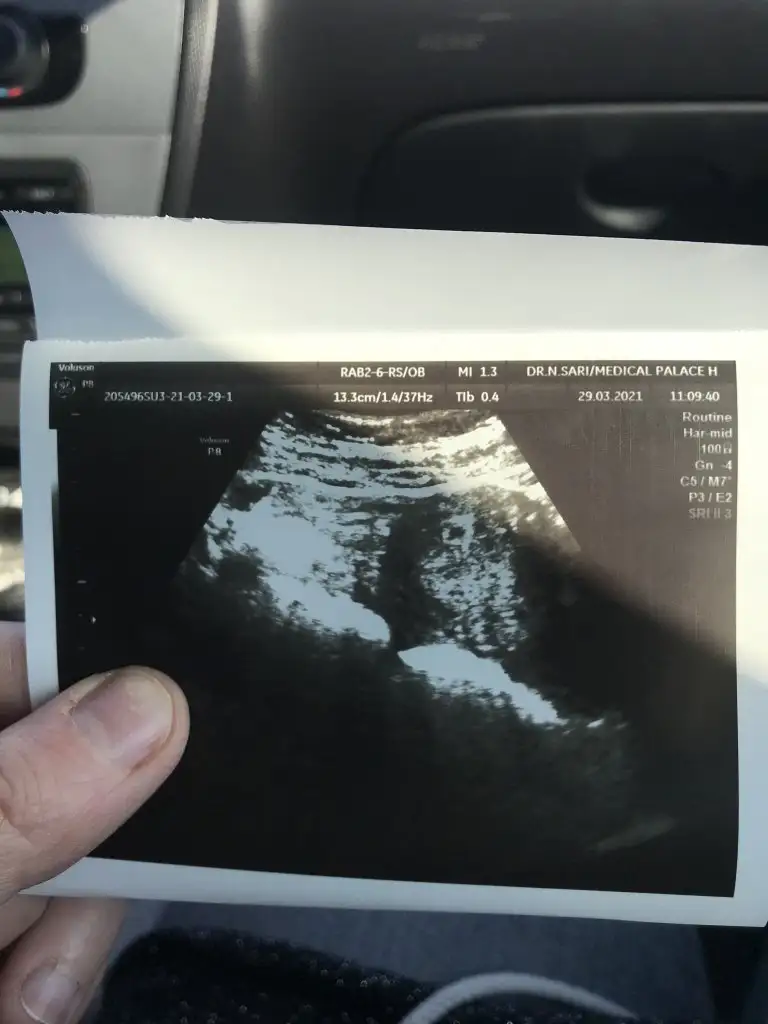

Banada bakar mısın canim 8+2 yiz

Eklentiler

• IMG-20210402-WA0003.webp

IMG-20210402-WA0003.webp

38 KB · Görüntüleme: 84